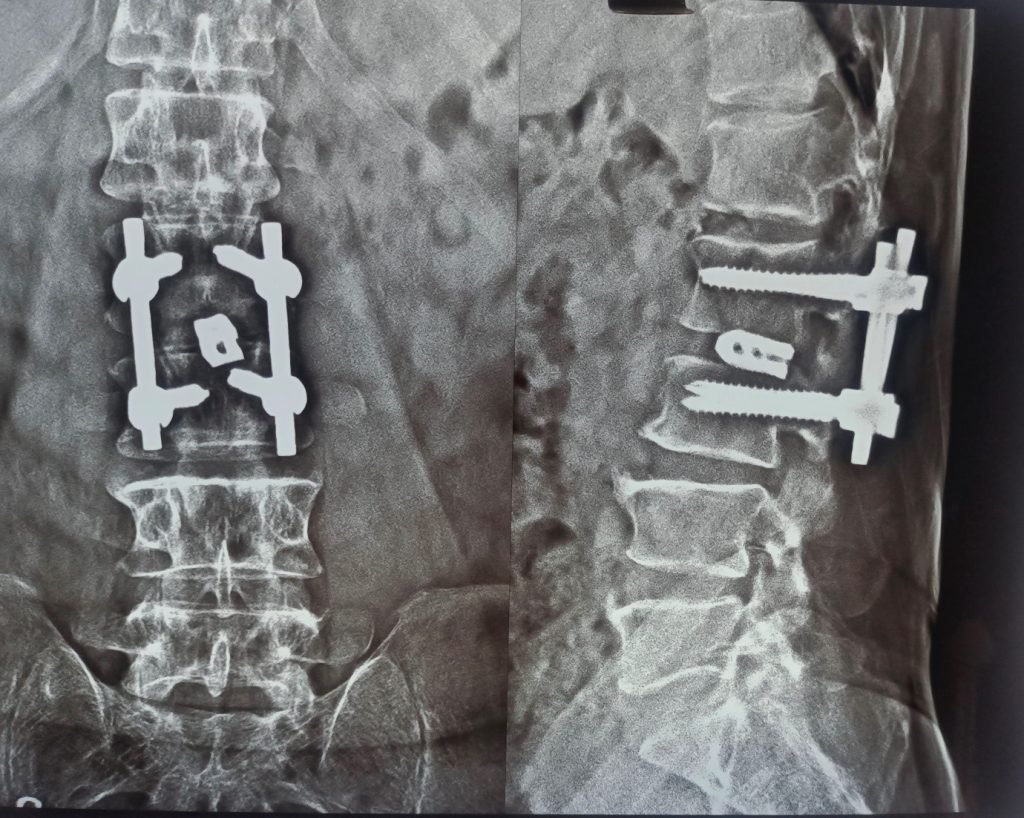

Treatment:

Complete removal of the affected disc with placement of a titanium disc or cage, followed by stabilization using titanium rods and screws for long-term support.